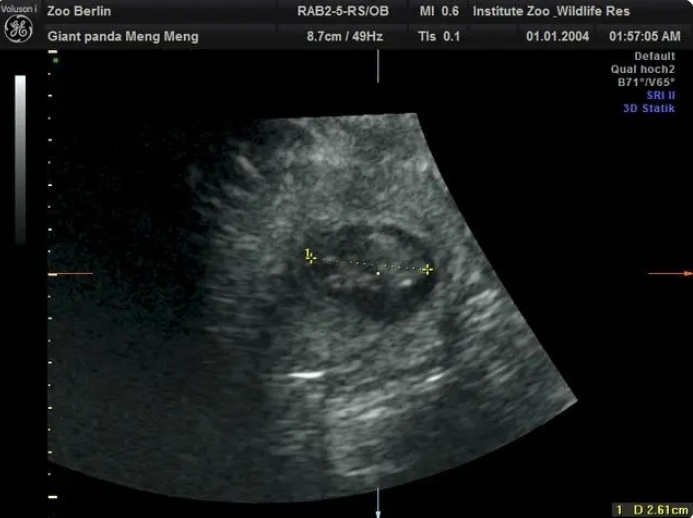

德國柏林動物園當地時間13日宣布,11歲的旅德大熊貓「夢夢」再次懷上雙胞胎。

在園方11日上午進行的超聲檢查中,工作人員清楚地檢測到兩個熊貓胎兒的心跳。目前兩個胎兒身長約2.5厘米。

柏林動物園介紹,根據目前胚胎的大小,如果一切順利的話,大熊貓雙胞胎預計將於8月底出生。